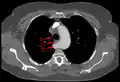

Aberrant subclavian artery

Aberrant subclavian artery, or aberrant subclavian artery syndrome, is a rare anatomical variant of the origin of the right or left subclavian artery. This abnormality is the most common congenital vascular anomaly of the aortic arch,[1] occurring in approximately 1% of individuals.[1][2][3]

This condition is usually asymptomatic.[1] The aberrant artery usually arises just distal to the left subclavian artery and crosses in the posterior part of the mediastinum on its way to the right upper extremity.[2] In 80% of individuals it crosses behind the esophagus.[2] Such course of this aberrant vessel may cause a vascular ring around the trachea and esophagus. Dysphagia due to an aberrant right subclavian artery is termed dysphagia lusoria, although this is a rare complication.[2][3] In addition to dysphagia, aberrant right subclavian artery may cause stridor, dyspnoea, chest pain, or fever.[1] An aberrant right subclavian artery may compress the recurrent laryngeal nerve causing a palsy of that nerve, which is termed Ortner's syndrome.[4]

The aberrant right subclavian artery frequently arises from a dilated segment of the proximal descending aorta, the so-called Diverticulum of Kommerell (which was named for the German radiologist Burkhard Friedrich Kommerell (1901–1990), who discovered it in 1936).[5][6] It is alternatively known as a lusorian artery.[1][3]